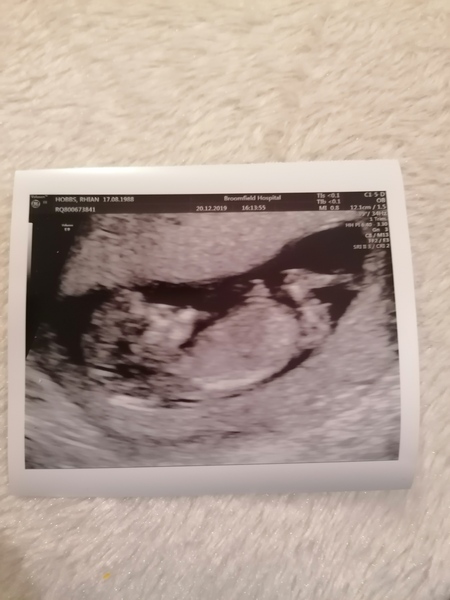

So had my scan yesterday and after all the worrying, my little squidge is all confirmed! Due 2nd July. Going to tell my eldest son today, he had said throughout the year that he hoped for another brother or sister so we can't wait to tell him!

showmewhatyougot · 21/12/2019 16:24

@MRSRCH lovely scan! But just Incase you didn't realize it has your name and details on it